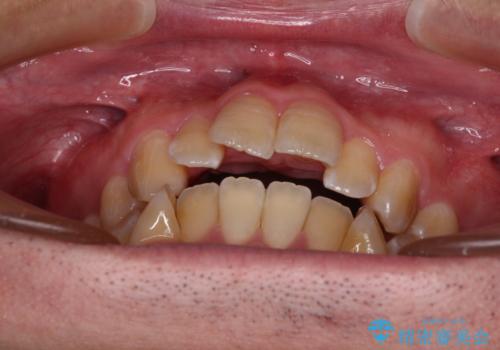

オープンバイトをインビザラインで矯正治療

- 前歯の開咬を気にして来院された患者様です。

開咬の治療は、前歯を閉じるように動かすとともに、上下臼歯を圧下(骨内にめり込ませる)させることで進めて行きます。

インビザラインは臼歯の圧下を効果的に行えるため、インビザラインを用いて矯正治療を行うこととしました。

オープンバイトは舌の突出癖により誘発され、治療後も突出癖が残っている容易に後戻りしてしまいます。

治療期間を短縮するためにも、舌突出癖の改善が極めて重要となります。

特にインビザラインではIPRという歯と歯の間を削る処置を多用するため、後戻りによりスペースが生じやすくなるため、治療初期段階での舌のトレーニングが必須となります。